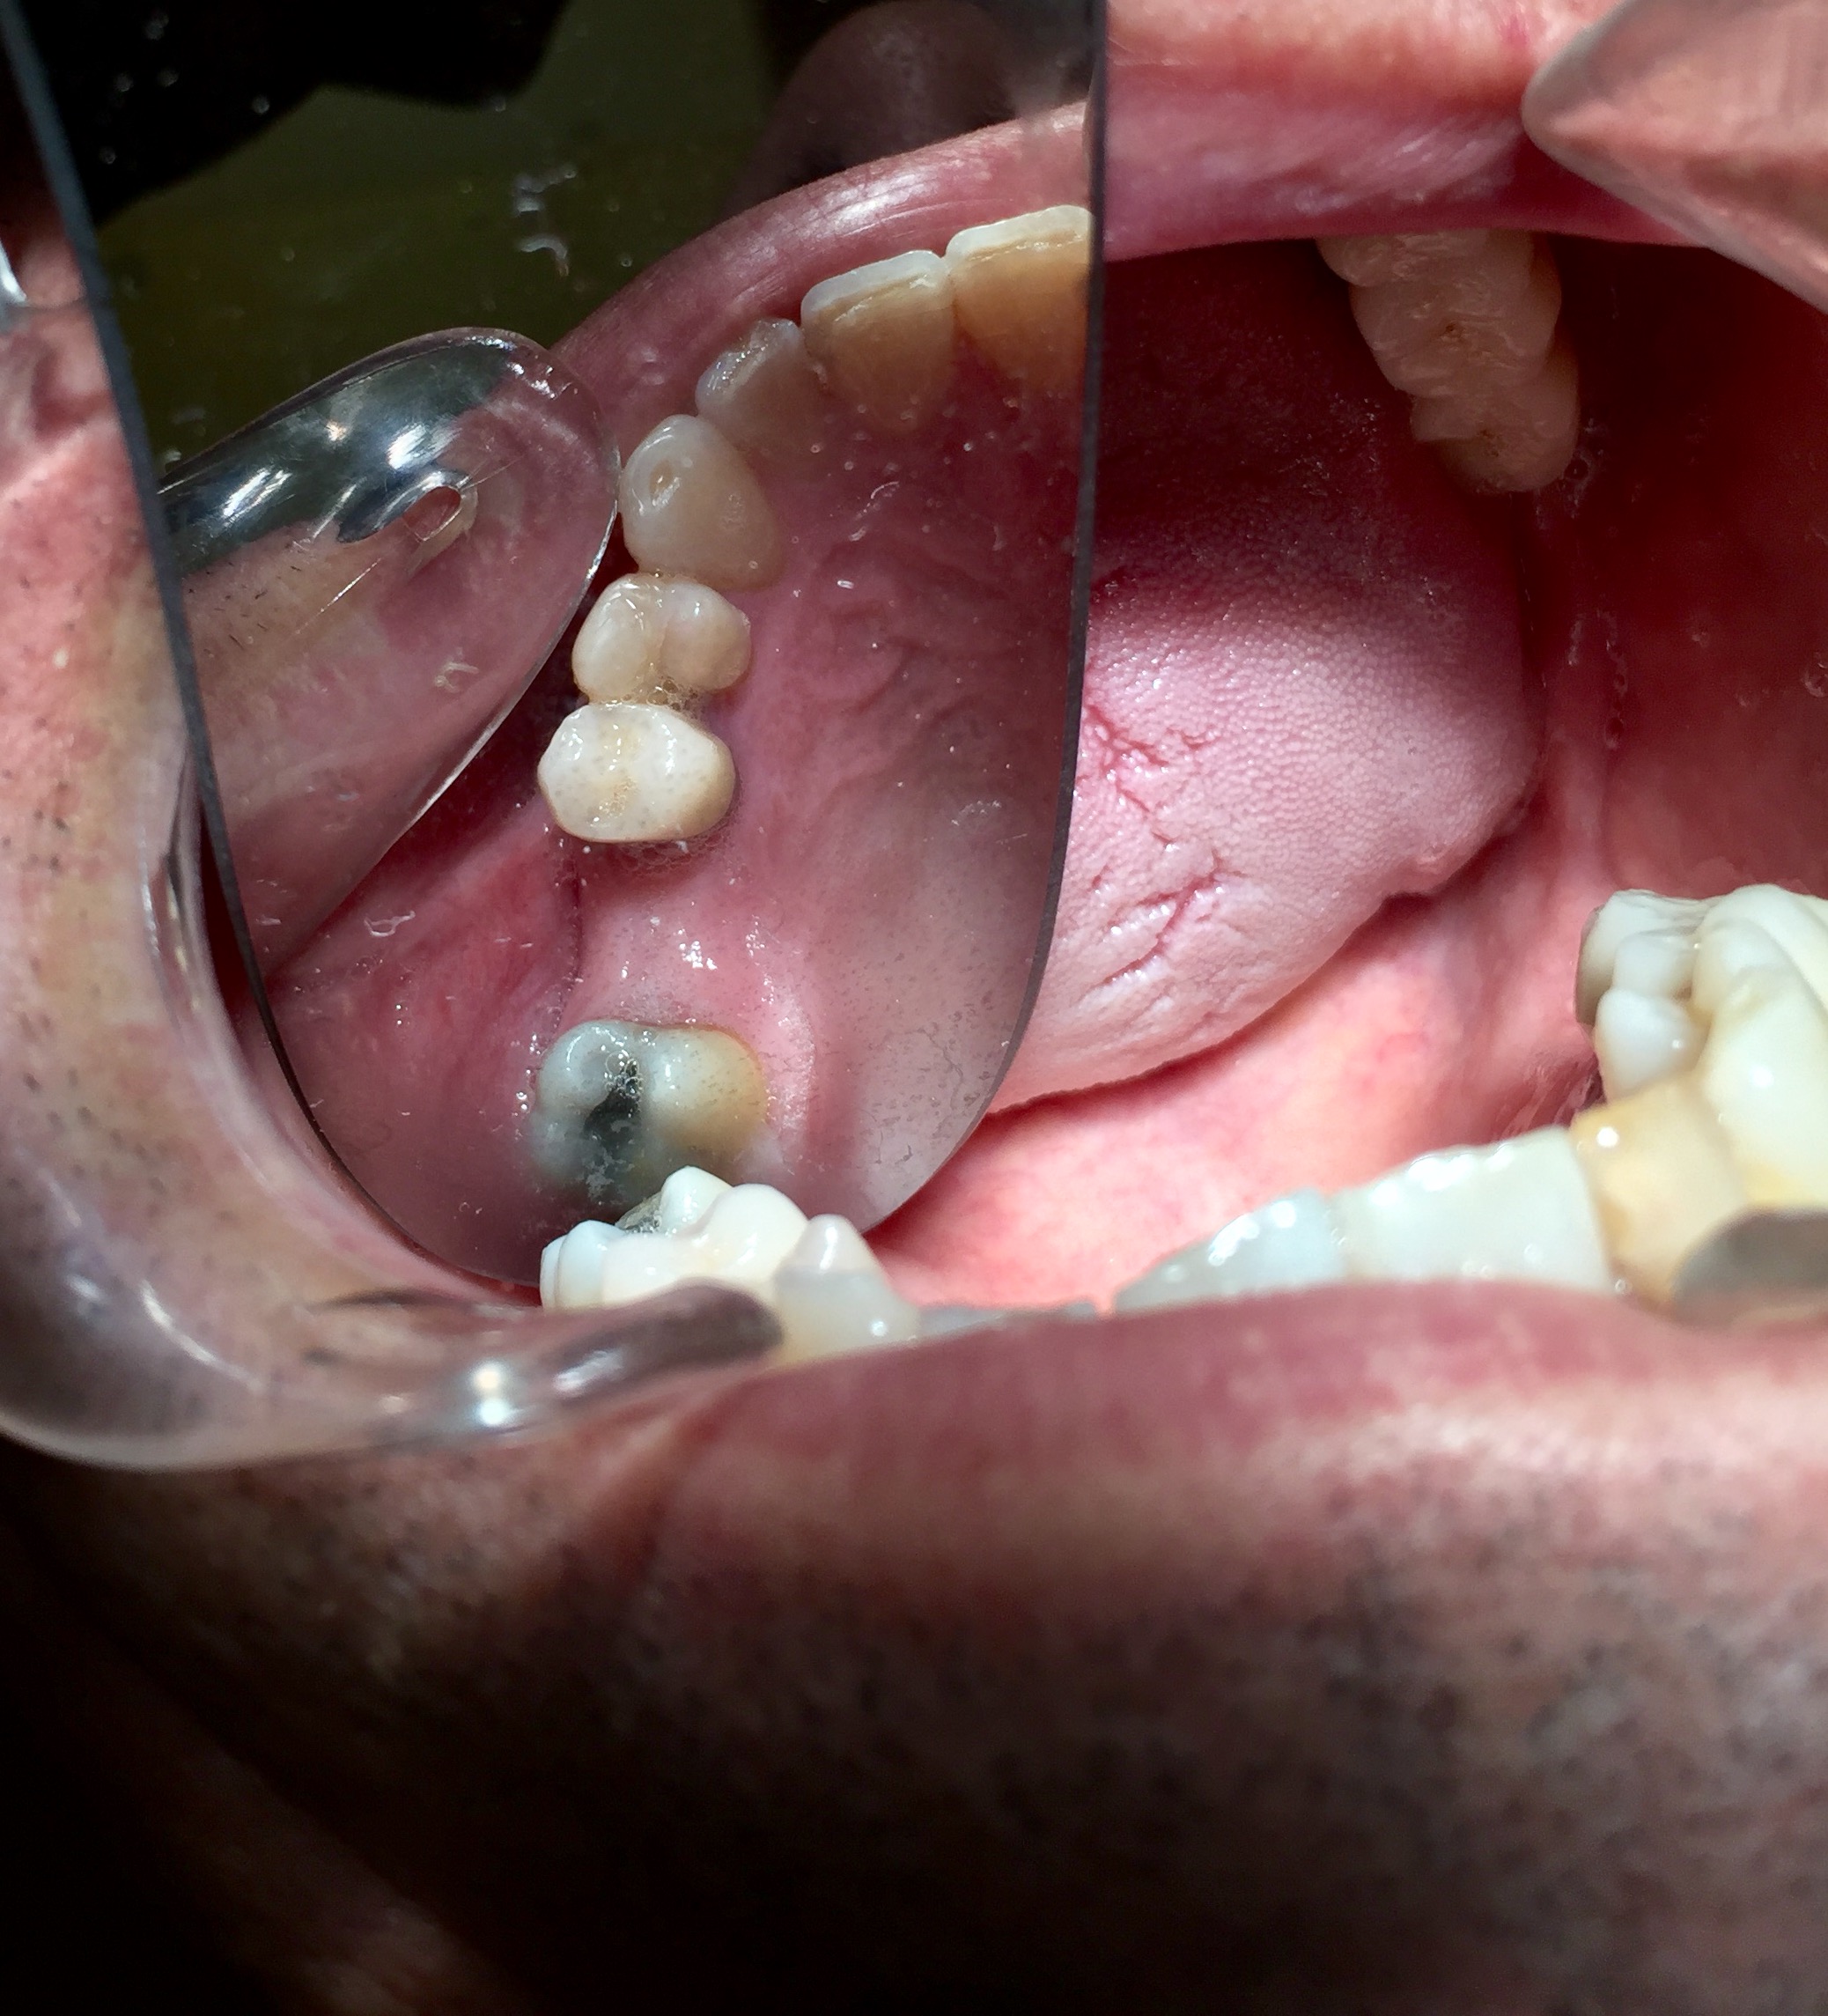

Protesi mobile dell'Arcata superiore